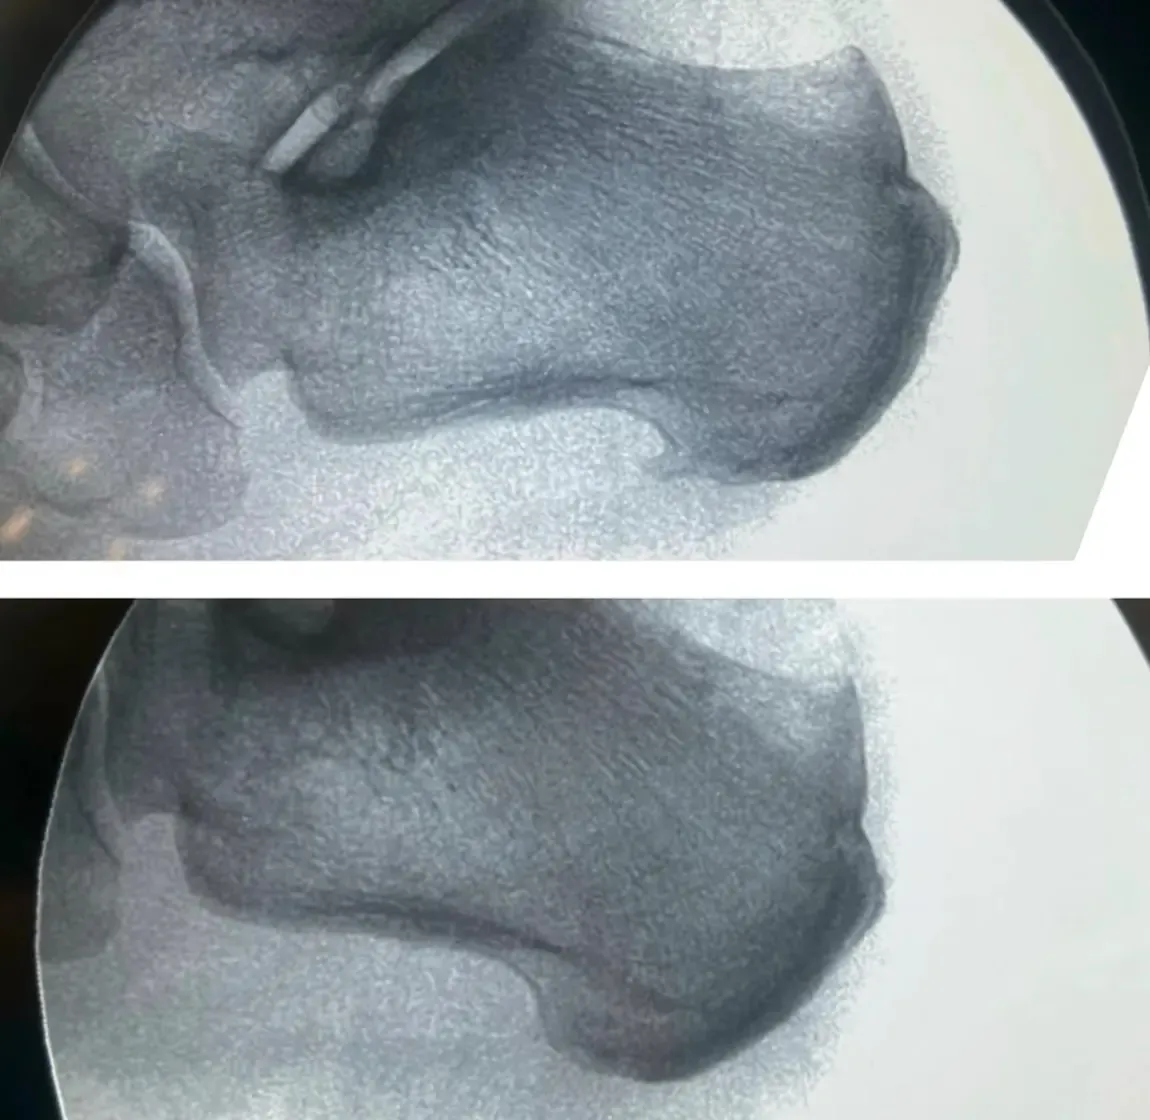

Espolón Calcáneo

Dolor intenso en el talón al pisar, especialmente por las mañanas.

Me Duele el Talón Común

Dolor de talón: fascitis plantar, espolón calcáneo y otras causas frecuentes.